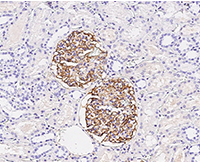

Anti-CR1/CD35, Rabbit pAb: (Cat#: 100464-T08)

Application: IHC-P

Immunochemical staining of human CD35 in human kidney. Image Credit: Sino Biological Inc.